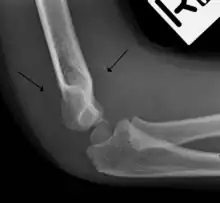

Fat pad sign

The fat pad sign, also known as the sail sign, is a potential finding on elbow radiography which suggests a fracture of one or more bones at the elbow. It is may indicate an occult fracture that is not directly visible. Its name derives from the fact that it has the shape of a spinnaker (sail).[1] It is caused by displacement of the fat pad around the elbow joint. Both anterior and posterior fat pad signs exist, and both can be found on the same X-ray.

The fat pad sign is invaluable in assessing for the presence of an intra-articular fracture of the elbow. An anterior fat pad is often normal. However a posterior fat pad seen on a lateral x-ray of the elbow is always abnormal. The patient will be unable to flex their elbow and requires orthopaedic input.[2]